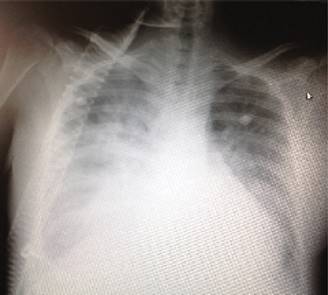

Mujer de 21 años con carga genética materna y paterna para diabetes mellitus tipo 2. Antecedente de diabetes mellitus tipo 1 en tratamiento con dieta e insulina 10 unidades subcutáneas de acción intermedia (NPH) por la mañana y 10 unidades NPH más 4 unidades de insulina de acción rápida por la noche. Antecedentes ginecoobstétricos: cinco gestas, dos partos, dos abortos, grupo sanguíneo O Rh positivo. Menarca: 12 años. Ritmo 35 × 7 días. No uso de método de planificación familiar. Embarazo de 30 semanas de gestación por amenorrea, acude al Servicio de Urgencias por presentar actividad uterina, signos vitales a la exploración física: tensión arterial 150/90 mmHg, frecuencia cardiaca 92 por min, frecuencia respiratoria 20 por minuto, temperatura 36.7o, paciente tranquila, consciente y orientada, sin alteraciones cardiorrespiratorias, abdomen con útero gestante con fondo uterino de 29 cm, frecuencia cardiaca fetal (FCF) 156 por minuto, al tacto vaginal cérvix central, blando, con 10 cm de dilatación, se traslada a la Unidad Tocoquirúrgica donde se atiende parto pretérmino obteniendo recién nacido femenino de 1,530 gramos, talla 42 cm, APGAR 7/8 SA. 0 Capurro de 30.2 semanas de gestación, con sangrado de 500 cc postparto. En el puerperio inmediato presenta descontrol hipertensivo 160/110 mmHg, FC 146 por minuto, FR 26 × minuto, disnea, temperatura de 37.6o, índice de proteínas urinarias/creatinina urinaria de 0.3, proteínas en labsctik ++, ingresando a Unidad de Cuidados Intensivos (UCI) con diagnóstico de preeclampsia severa/emergencia hipertensiva con edema agudo pulmonar, iniciando tratamiento antihipertensivo intravenoso con nitroprusiato de sodio y vía oral con alfametildopa 500 mg vía oral cada ocho horas, e hidralazina 50 mg vía oral cada seis horas, persistiendo incremento de trabajo respiratorio, saturación por oximetría de pulso 83% con FiO2: 33%, gasometría arterial; pH 7.37 pO2 56 pCO2 24 HCO3 18.2 Sat: 85% déficit base -5.2, lactato sérico 2.1, con trastorno mixto de acidosis metabólica, con alcalosis respiratoria, insuficiencia respiratoria tipo I, por lo que se decide colocar en ventilación mecánica no invasiva PS/CPAP con los siguientes parámetros (PS) presión soporte de 12 cmH20, CPAP o PEEP 5 cmH2O FiO2: 60%, disminuyendo trabajo respiratorio, aumentado la oximetría de pulso ≥ 94%, radiografía de tórax en la cual se observan datos de edema agudo pulmonar (Figura 1).